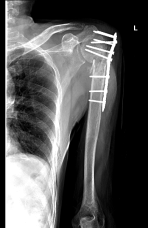

患者是一位63岁的男性,2019年12月中旬外出活动时走路滑到摔伤后左肩部肿痛畸形不能活动,当时在外院诊断为左肱骨近端骨折,行左肱骨近端骨折切开复位内固定术。2020年1月31日患者被电动车碰撞,再次摔伤左肩部,来我院就诊,骨伤科黄刚主任接诊,经检查后发现左肱骨近端粉碎性骨折,严重骨质疏松症,原左肱骨近端骨折内固定钢板螺钉失效,骨折部粉碎、移位大。

骨伤科黄刚主任介绍,如再行传统的“切开复位内固定术”治疗,复位困难,肱骨头后期坏死、不愈合的可能性非常大,给骨折后期的功能康复带来巨大的隐患,将会影响患者日常生活,经过科内专家病例讨论,认为目前最适宜的治疗方法是实施反置式人工全肩关节置换术。